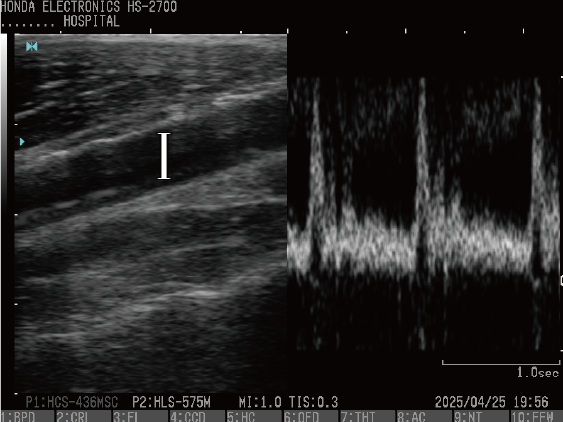

PW(パルスウェイブドプラ)

プローブ:HLS-575M